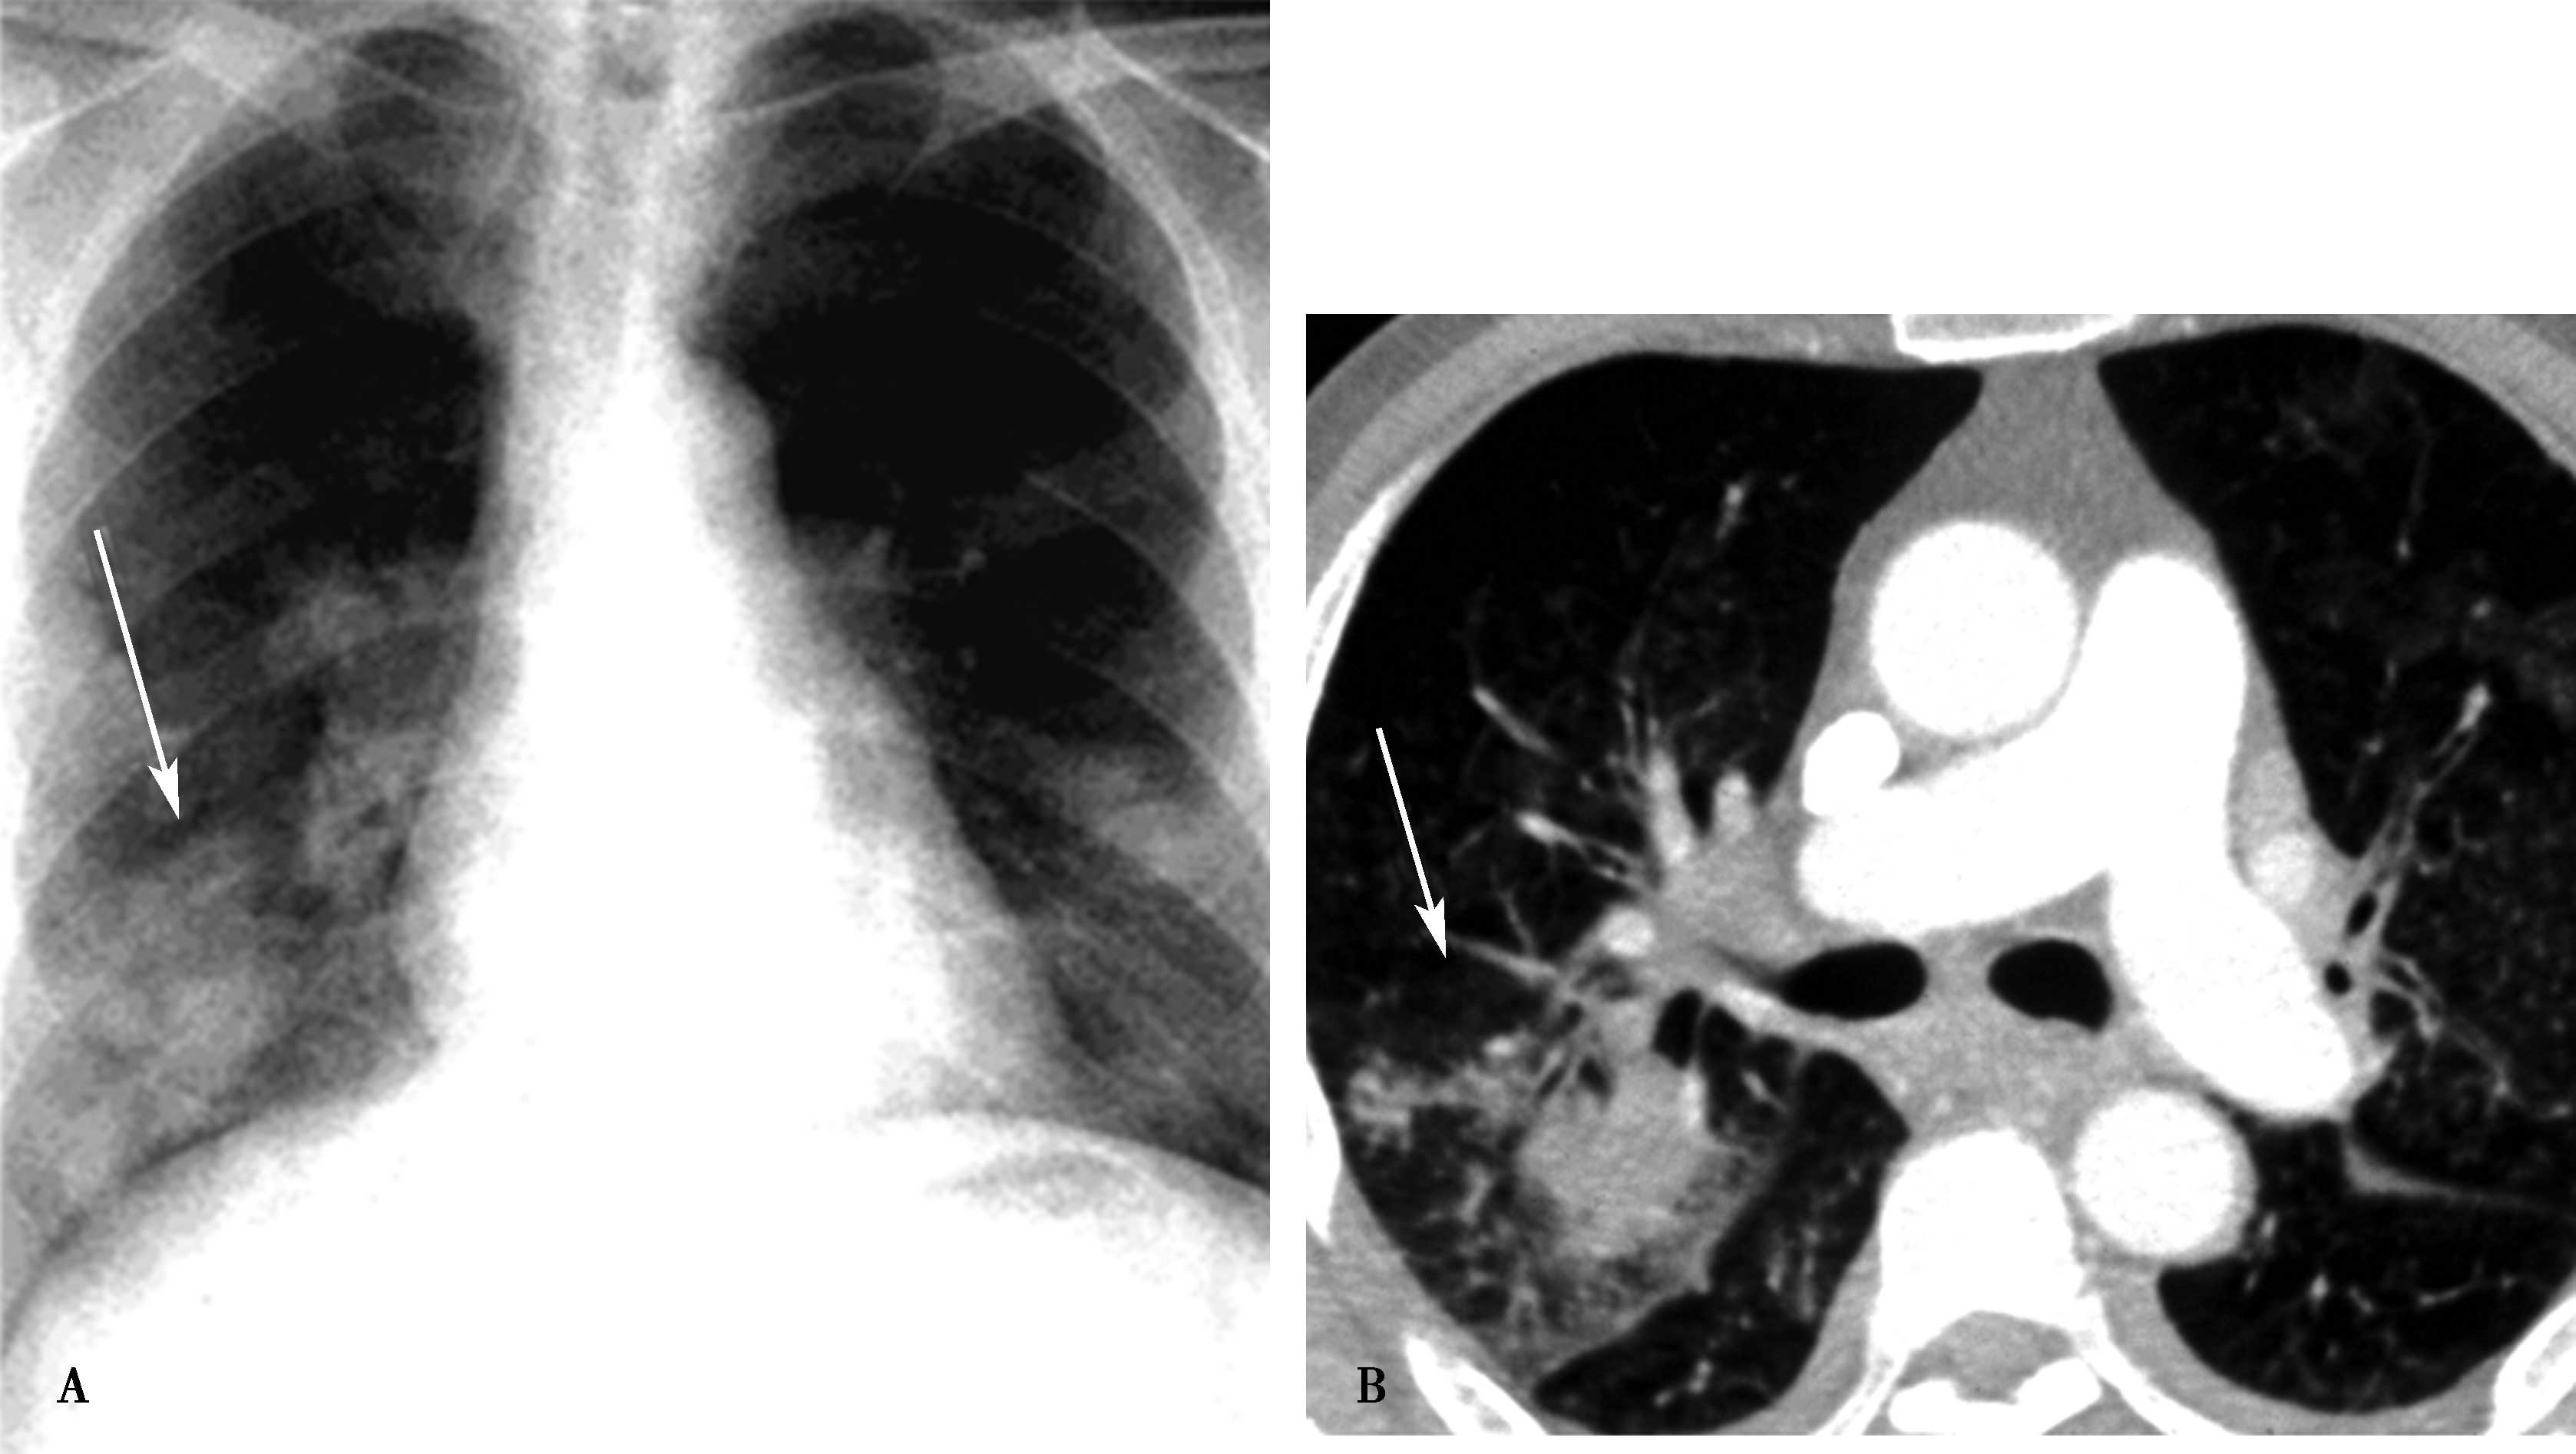

图7-2-7 右肺上叶及中叶肺水肿(间质性及肺泡性肺水肿)

造影证实为右上肺静脉闭塞;A.胸部正位;B.HRCT冠状位重建,可见典型小叶间隔增厚(↑),肺泡性水肿(▲)